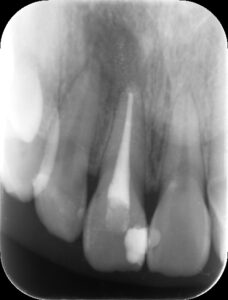

根管充填後6か月のレントゲン。根尖部の黒いX線透過像は完全に消失している。